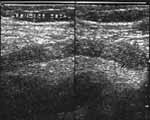

· Не поддающаяся компрессии трубчатая структура с одним слепым концом (Рис. 6).

· В поперечном сечении напоминает мишень. Если аппендикс изогнут, то при поперечном сканировании возникает картина, напоминающая митоз клеток (Рис. 7).

· Максимальный наружный диаметр превышает 6 мм.

· При заполненном аппендиксе максимальная толщина стенок превышает 3 мм.

Увеличить

Рис. 6. Воспаленный аппендикс диаметром 0,74 см в продольном сечении. Положение датчика косое.

Рис. 7. Поперечное сканирование воспаленного (диаметр 0,89 см.) изогнутого (на снимке дважды видно поперечное сечение) аппендикса.